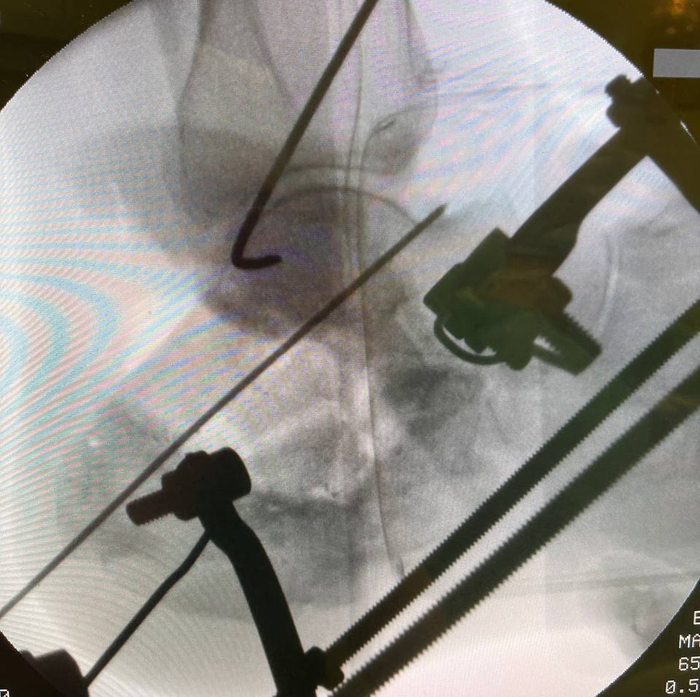

Всегда в начале операции выполняю прицелочный снимок, чтобы наглядно видеть с чего мы начинали.

Подобным образом выглядит ЭОП-снимок на этапе удаления металлоконструкции и склерозированной кости. Можно видеть силуэт дистрактора Хинтермана, который я использовал на данном этапе для временной дистракции подтаранного сустава, чтобы обеспечить лучшую визуализацию. Мы видим насколько уменьшился объем пяточной кости по сравнению с первоначальном этапом. Это результат резекции в пределах жизнеспособной кости. Жизнеспособность кости оцениваю исключительно макроскопически по наличию губчатой структуры и кровяной расы (да, под жгутом она тоже есть).

Этапный снимок с установкой аппарата.